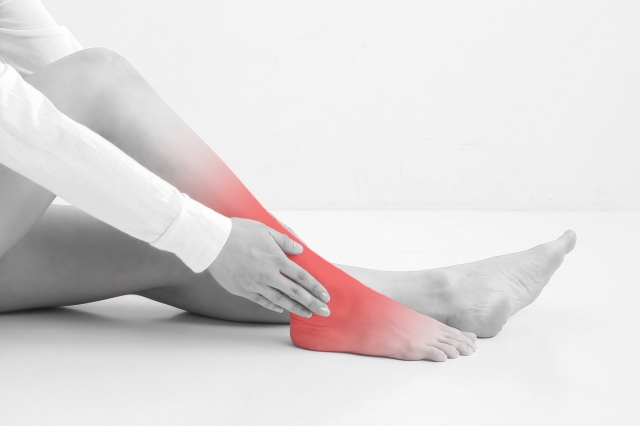

下肢静脈瘤は

多くの方が

悩まれていますね💦

ふくらはぎ周辺は下肢静脈瘤も

起こりやすいですよね。